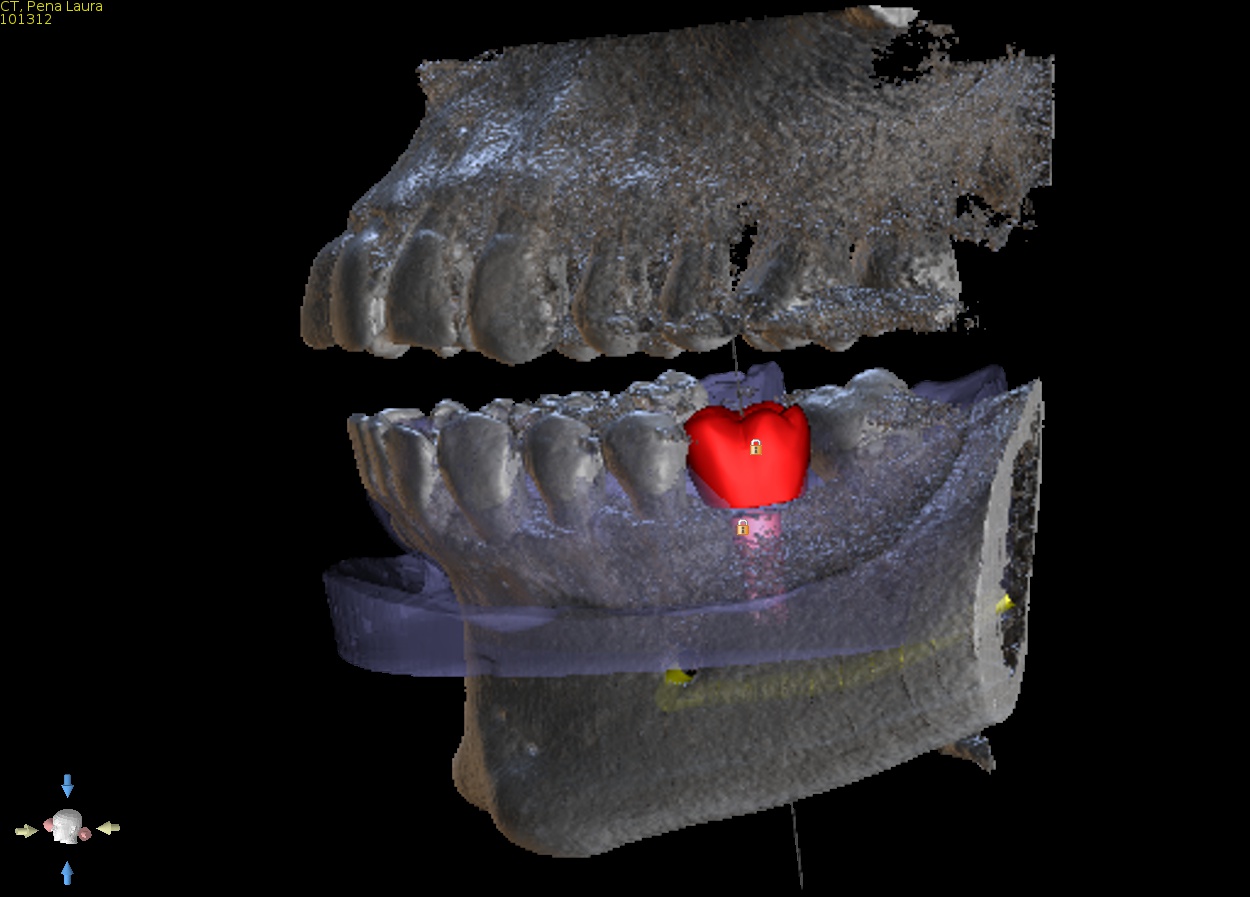

2. Virtual implant placement

Supply us with the implant brand and size and we will position it exactly to your specifications and in relation to the virtual final tooth position. We will send a written report for you to check and note any changes if needed. We will not make the guide until you are 100% satisfied with the virtual placement. Alternatively use free software to plan the case yourself and send us the plan file and we can make the guide from that.

3. Approval of implant report

Approve the plan so construction of the implant guide can go ahead, this must be done via replying to our email. Let us know what type of guide you wish to select and what size of drills you will be using. See next point for more information on types of guides.

Approve final implant report via email.